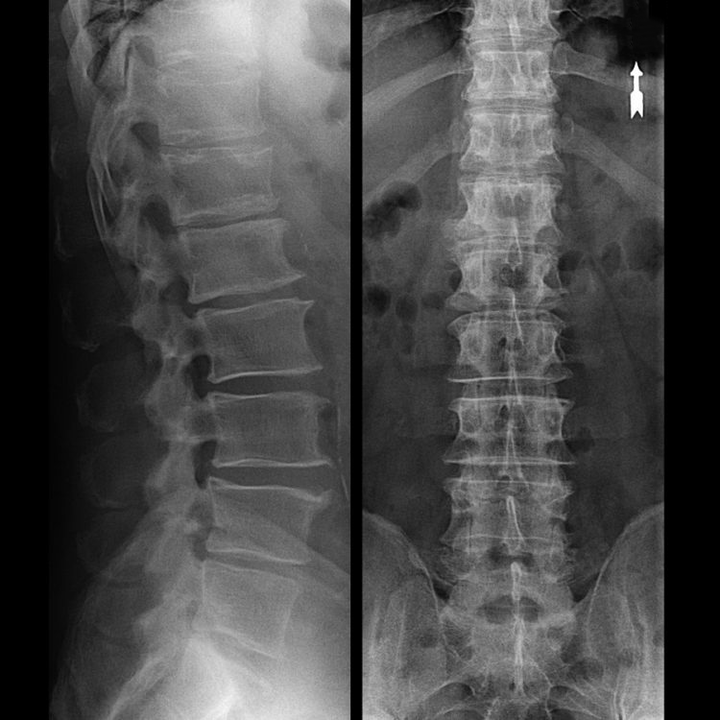

In typical cases, osteochondrosis of the cervical and cervicothoracic spine occurs as described above.Therefore, the main stage of the diagnosis was and remains the identification of the patient's complaints, establishing the presence of simultaneous muscle spasm by simply palpating the muscles along the spinal column.Can the diagnosis of osteochondrosis be confirmed by X-ray examination?

"X-rays" of the cervical spine and even flexion and extension functional tests do not detect cartilage because their tissue transmits X-rays.Nevertheless, based on the location of the vertebrae, general conclusions can be drawn about the height of the intervertebral discs, the general straightening of the physiological curvature of the neck - lordosis, and the presence of marginal growths on the vertebrae, which cause long-term irritation of their surface by the fragile and dehydrated intervertebral discs.Functional tests can confirm the diagnosis of cervical spine instability.

Since the discs themselves can only be seen with CT or MRI, magnetic resonance and X-ray computed tomography are recommended to clarify the internal structure of the cartilage and formations such as protrusions and hernias.Thus, with the help of these methods, the diagnosis is accurately established, and the results of the tomography are an indication and even a current guideline for the surgical treatment of hernia occurring in the neurosurgery department.

- You can regularly take at least an x-ray of the lumbar spine in two projections or an MRI to see if the hernia, if any, is progressing;